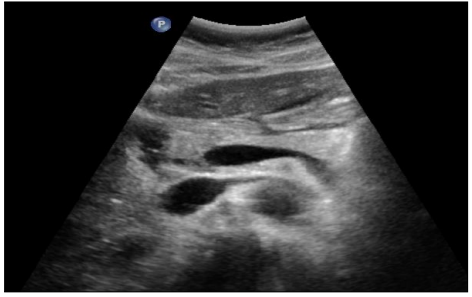

Pancréas

ANNET L. - UCL

Digestif MASTER 1 Pancreas